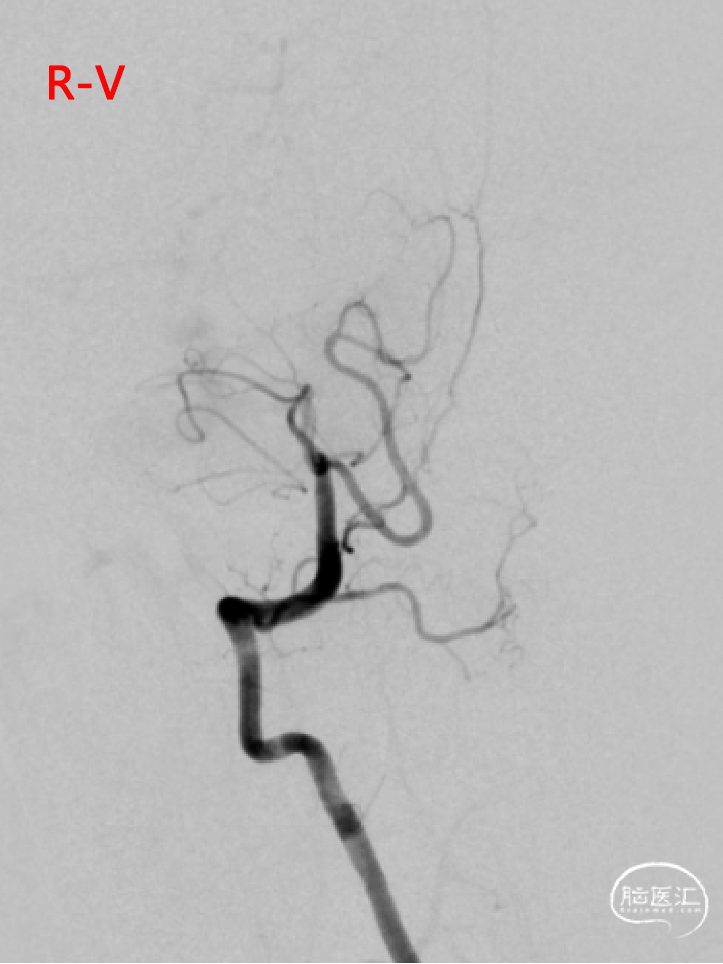

➢DSA(2023.11.10)

R-DAS技术超选右侧颈内,右侧颈内动脉血管迂曲。